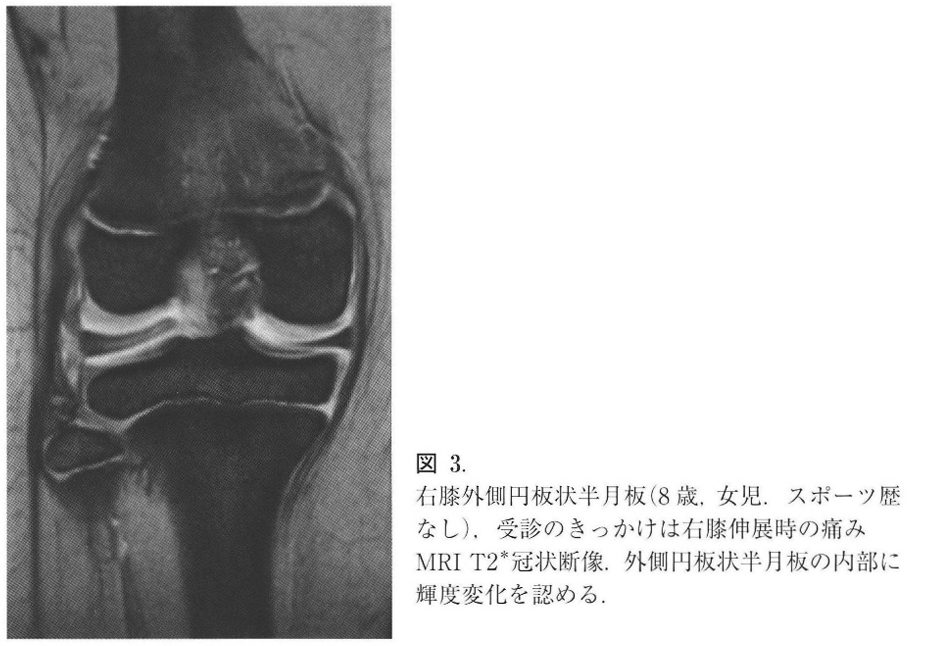

半月板とは膝の骨と骨の間のクッションの役割をする構造物ですが、胎児の頃はまん丸の形をしていて成長とともに徐々に三日月の形になっていきます。円板状半月とはイメージで言うと半月板がまん丸のまま残っているような状況です。ですので、骨と骨の間に挟まれて損傷し膝の痛みになりやすい方が一定数いらっしゃいます。

また円板状半月板は外側半月板がほとんどで、正常の半月板よりも厚く、内部の線維配列も異常で損傷を受けやすく、損傷すると伸展障害、膝の外側の痛み、ひっかかりなどが生じます。

診察とレントゲン、MRIで診断します。診察では痛みの場所、膝をひねったときに痛くないかなどをチェックし、レントゲンでは骨の異常がないかを確認します。最終的にMRIを撮影し、確定診断となります。

まずは安静、サポーター、痛み止めの処方を行い、炎症を抑えることから治療を始めます。痛みが落ち着いた場合はリハビリを行い、膝周囲の筋力を上げ、損傷部位に負担がかからないように生活指導も行います。それでも痛みが改善ない場合は手術で、余分な半月板を切除し縫合する半月板形成術を行うことが多いです。そのような場合は提携している病院へ紹介させていただくこともございます。